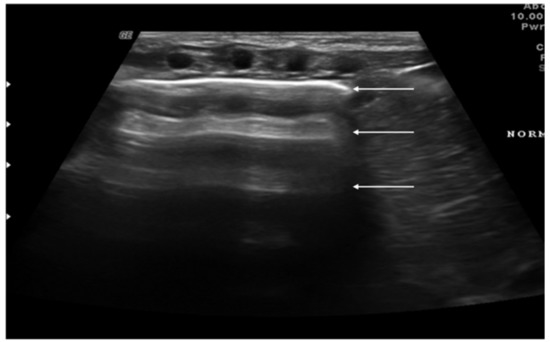

“A-lines” represent some of these artifacts that can be found in a completely healthy lung (Figure 1) [14]. They are horizontal echogenic lines equidistant and parallel to each other and the pleura, representing reverberations of the pleura itself that arise when the ultrasound beam reflects off of the pleura and partially reflects off of the probe face back to the pleura again before getting back to the machine instead of entering the probe. They are caused by the large difference in acoustic impedance between the pleura and the air contained in the lungs. The distance from each other is related to the distance between the pleural line and the skin surface, and their position does not change with respiratory acts.

Figure 1.

Appearance of a healthy lung. White arrows show pleural and A-lines.